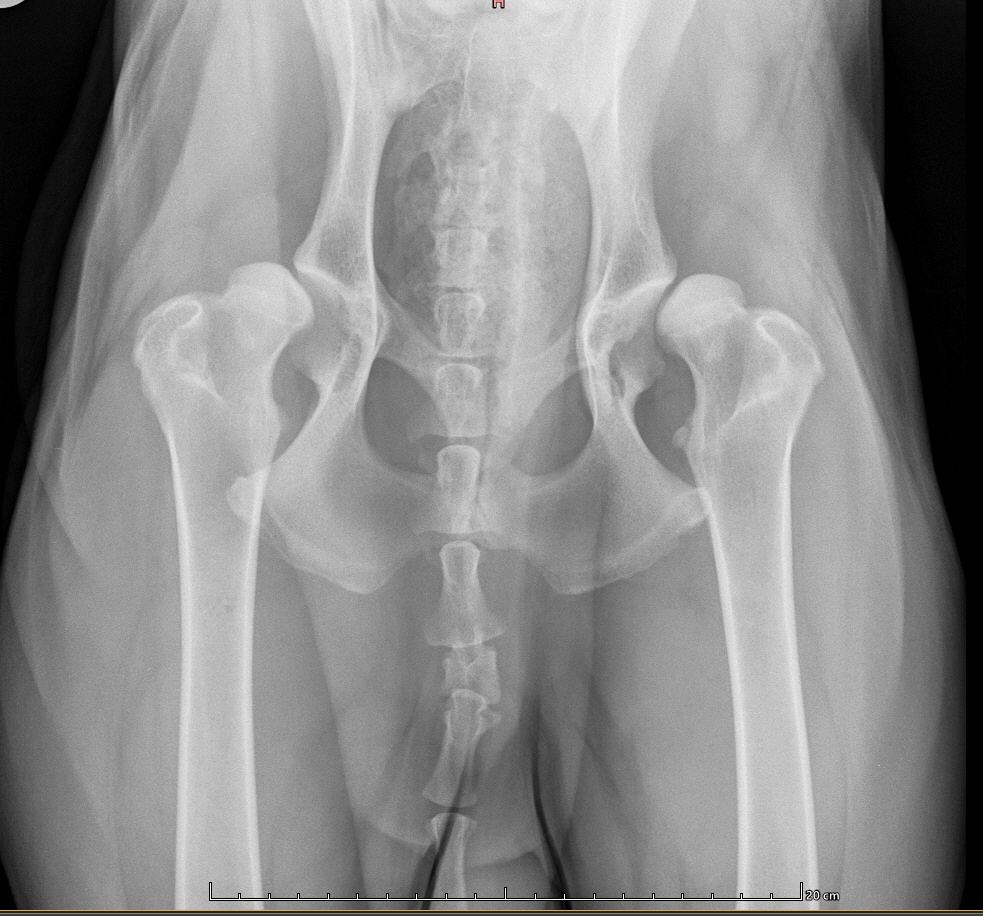

Digitales Röntgen

Wir Röntgen digital

Das digitale Röntgen bietet eine Reihen von Vorteilen

weswegen wir uns dazu entschieden haben, Ihnen

diesen Service anzubieten.